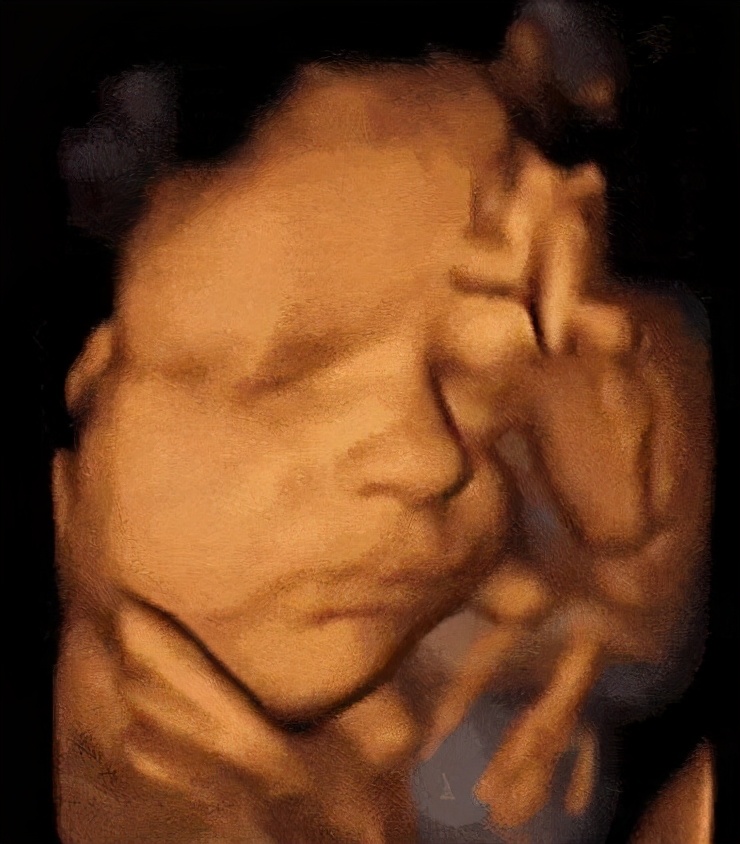

三维图像是这样的